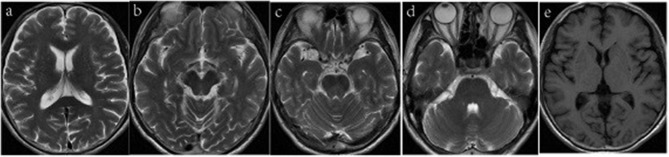

Results: Specifically, muscle rigidity in ALS is characterized by a velocity-dependent increase in muscle tone caused by damage to the upper motor neurons. This symptom tends to be more pronounced in the lower limbs than in the upper limbs and is often accompanied by spastic gait. Objective examinations may reveal early atrophy of the frontal and temporal lobes of the cerebrum on head magnetic resonance (MR) imaging, whereas 18F-FDG brain positron emission tomography (PET) may reveal reduced metabolism in the frontal and parietal lobes of the cerebrum with normal basal ganglial function, distinguishing ALS from basal ganglial metabolic decline in MSA.

Discussion: To our knowledge, this is the first case of ALS misdiagnosed as MSA. Clinically, patients with parkinsonism who do not respond to dopaminergic drugs should be cautious about atypical ALS. Muscle rigidity manifesting as upper motor neuron damage, and MR and 18F-FDG brain PET imaging can provide early differential diagnosis indicators.